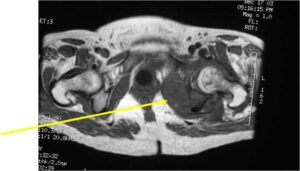

Sites:

- Most common in pelvis, proximal femur, proximal humerus, distal femur, ribs

Radiology emulates pathology: Biphasic Tumor

- One region low grade chondrosarcoma

- Second more aggressive area with bone destruction, lysis of calcification, soft tissue mass

- Cortical permeation and a soft tissue mass in 70% of cases

Characteristically abrupt transition between chondroid tumor and dedifferentiated, lytic component